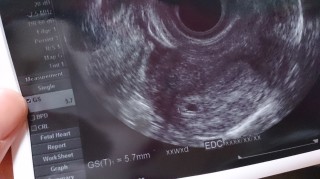

5w5dだと思って行きましたが、排卵日が一週間近くズレたようで、まだ豆粒でした。大きな丸になるのかまだまだ不安ですが、信じて待ちます。

5週5日くらいだと思ったら、まだ、4週5日でした。2回目の受診でしたが、胎嚢が確認出来てよかった。大きさは13.7ミリでした。1週間後には心拍が確認できるみたいで楽しみです。

はっきりした週数は言われませんでしたが4週目後半とのこと。まだ5.7mmでしたがしっかりと胎嚢確認とれました!次の受診は2週間後です(^^)